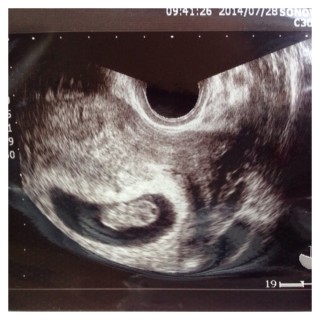

初めての妊娠です。エコーで赤ちゃんが動いてるのを見た時、すごく嬉しかったです。次の検診まで何日かありますが、成長している姿が見れる事を期待しています。

今回初めて手足がはっきり見えました!くねくねと動いているのがあまりにも可愛くて笑ってしまいました(^O^)次回も楽しみです♪

手足をピクピク動かしてました☆